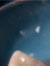

Figura 2. Radiografía tridimensional basal donde se aprecia la ausencia de tabla vestibular en el diente en posición de 41.

Figura 7. Cambios radiográficos. a) radiografía 2D basal; b) radiografía 2D 12 meses.

Figura 1. Caso clínico 1. Situación clínica basal de una paciente que presenta recesiones gingivales con pérdida de inserción interproximal en el quinto sextante. A la exploración se observa una profundidad de sondaje incompatible con salud en centro-vestibular del diente en posición de 41, presumiblemente combinado con una dehiscencia ósea.